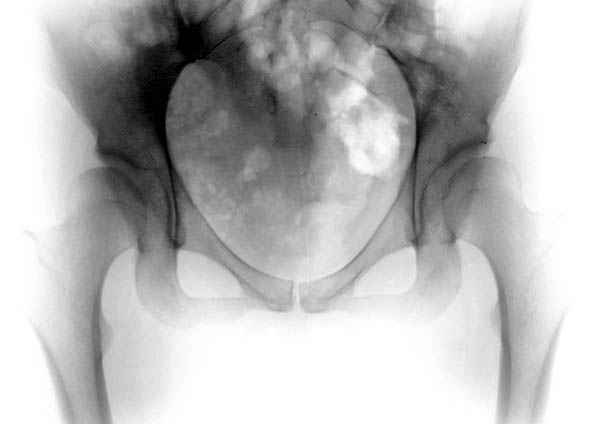

Похоже, это типичная кистовидная перестройка на фоне диспластического артроза.

Рентгенограмма здесь дает достаточно информации для осознания бесперспективности консервативного лечения - более чем очевидный дефицит покрытия головки, coxa valga и т.д. Никакое консервативное лечение, и "протезы синовиальной жидкости" в том числе, эту проблему не решит. Конечно, если пациента обезболить и поставить на костыли на несколько недель, это улучшит его самочувствие на какое-то время. А если думать о долгосрочной перспективе - надо планировать хирургическое лечение.

Иван, да тут угол Виберга 0 градусов. Какое уж консервативное лечение. Кистозная перестройка - типичный компенсаторный (?) процесс при такой дисплазии.

Картина типичной эволюции дисплазии сустава "кистовидная перестройка", на фоне неправильного взаймоотношения сустава "да тут угол Виберга 0 градусов" на вершине наибольшей нагрузки в вертлужной впадине образовался участок разрежения, "киста", в последующем через этот участок образуется перелом - стадия фрагментация дисплазии.

Для установки диагноза достаточно информации, на рентгенограмме передний и задний край ацетабулум образовали перекрест, "цифру восемь", указывающий на небольшую ретроверсию, а суставная щель одинаковой ширины на всем протяжении, что доказывает, что с покрытием хряща проблем нет. Головка бедра покрыта всего наполовину, это явное нарушения взаимоотношений.